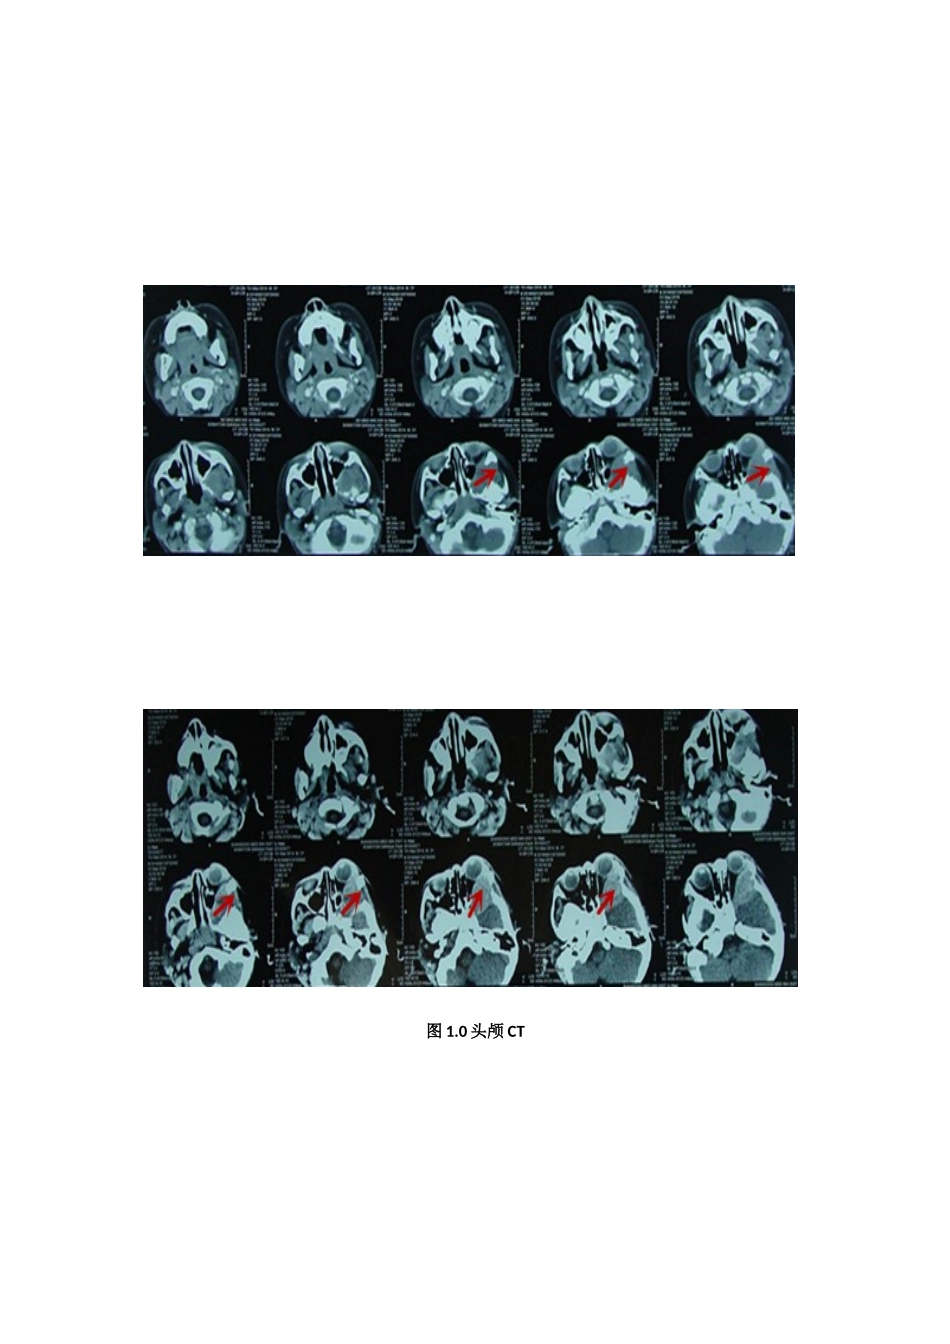

颅骨嗜酸性肉芽肿〔【实习医师汇报病历】〕〔患儿男性,1岁11月。因“左眼红肿2月余,加重伴左眼球突出20天”入院。患者家属待述:缘于2月前患儿无明显诱因出现左眼红肿,并伴有分泌物增多,视力未见明显异常,右眼正常。曾就诊于当地医院眼科,考虑感染,予以滴眼液滴眼处理(具体不详)患儿病情未见明显改善,约于20天前患儿左眼红肿体征明显加重,伴有左眼球外凸。为求明确诊断就诊予于山东济南市眼科医院,行眼眶CT检查提示:颅中窝占位,建议手术治疗。〕〔体格检查〕体温(T)36.5℃,呼吸(R)20次/分,脉搏(P)100次/分,血压(BP)120/80mmHg。发育正常,头颅正常无畸形。右眼正常,左眼结膜充血、红肿,眼球外凸;双侧瞳孔等大等圆,直径3.5mm,对光反射灵敏,双眼视力、视野查体不合作。〔辅助检查〕眼眶CT提示(图1.0)显示:左侧眼眶外侧壁见梭形软组织密度肿块,边界清,周围骨质破坏吸收。头颅MRI(图1.1):左眶外侧壁见不均匀长T1稍短T2信号影,增强见大片不均匀强化;左侧眼球受压变形。图1.0头颅CT图1.1头颅MRI〔诊断〕颅内外沟通性占位病变(颞窝及眼眶,左),考虑嗜酸性肉芽肿可能性大。﹝治疗﹞完善术前准备,包括血常规等三大常规、凝血功能、肝肾功能、电解质检验,完善心电图、胸部X线片等常规术前评估。﹝主任医师常问实习医师的问题﹞目前考虑的诊断是什么?答:颅内外沟通性占位病变(颞窝及眼眶,左),性质有待于手术病理明确。目前的最佳治疗方案是什么?答:目前患者占位症状明确,患儿左眼结膜充血、红肿,眼球外凸,具有明确手术指征,手术治疗是最佳方案,应积极完善相关术前常规检查及准备,详细告知患儿家属手术必要性,并详细阐述相关手术风险及并发症。常规术前准备有哪些?答:①实验室检验,包括:血尿便常规,肝肾功,感染性疾病相关抗体筛查,输血全套等;②头颅CT平扫及三维重建;③颅骨X片;④心肺功能评估,如心电图,胸部X片等。要确诊该病变性质有哪些方案?答:①开颅手术,切除病变,行病理检查;②立体定向穿刺活检。【住院医师或主治医师补充病历】患儿男性,1岁11月。因“左眼红肿2月余,加重伴左眼球突出20天”入院。查体:发育正常,头颅正常无畸形。右眼正常,左眼结膜充血、红肿,眼球外凸;双侧瞳孔等大等圆,直径3.5mm,对光反射灵敏,双眼视力、视野查体不合作。余神经系统查体未见明显阳性体征。眼眶CT提示(图1.0)显示:左侧眼眶外侧壁见梭形软组织密度肿块,边界清,周围骨质破坏吸收。头颅MRI(图1.1):左眶外侧壁见不均匀长T1稍短T2信号影,增强见大片不均匀强化;左侧眼球受压变形。结合患儿病史及相关影像学检查,考虑颅内外沟通性占位病变,嗜酸性肉芽肿可能性大,可进一步完善相关检查及手术病检明确。【主任医师常问住院医师、进修医师或主治医师的问题】对该患者的诊断是否有不同意见?答:患儿颅内外沟通占位病变诊断明确,首先考虑颅骨嗜酸性肉芽肿,下一步应积极予以对症支持治疗,并完善相关术前准备,尽早手术切除病灶。简述嗜酸性肉芽肿的临床表现和诊断?答:此病多发于小儿和青年,男性多于女性。病人常有头痛、低热及体重减轻。颅骨好发于额骨、顶骨及颞骨,而枕骨少见。颅盖都可发现小肿物,逐渐增大。局部可有疼痛,但不剧烈。实验室检查可发现白细胞总数略增高,嗜酸性粒细胞增多,血沉加快。头颅X检查,可见圆形或椭圆形溶骨性破坏,边缘不规则与正常骨分界清楚。此病单发性病变需与结核、骨髓炎和颅骨表皮样囊肿相鉴别,而多发性病变需与骨髓瘤、转移瘤和黄脂瘤病等相区别。需和哪些常见病变进行鉴别诊断?答:1、颅骨动脉瘤样骨囊肿:病变呈囊状膨胀性骨质破坏,骨壳菲薄,破坏区一般可见多个含液囊腔,并可见液平面。病灶右肥皂泡状外观。2、颅骨骨囊肿:以中青年多见,起源于骨内或骨膜下,常与外伤刺激有关。3、颅骨骨纤维异常增殖症:好发于儿童及青年,男多于女。单发或多发,后者可伴有皮肤色素沉着,内分泌紊乱,女性可有性早熟,称Albright征群。颅骨病变多见于额骨、蝶骨及颅底部。颅骨外板隆起,表面光滑,内板呈嵴状。4、颅骨表样囊肿:又称颅骨胆脂瘤,多见于青壮年,颅骨...